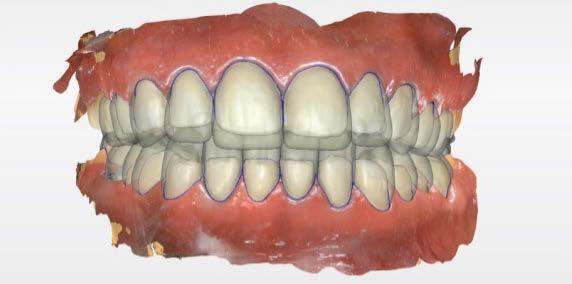

Terminada esta fase se elaboró una propuesta de diseño (CEREC,

SW 5.2, Dentsply Sirona) (Figuras 22-27), la cual fue materializada en dos tipos de materiales a partir de bloques cerámicos IPS Empress CAD y cerámica vítrea de disilicato de litio IPS E.max CAD (Figuras 28-30)

Figura 7. Modelado digital. Figura 9. Propuesta de diseño en oclusión Figura 10. Vista lateral derecha. Figura 8. Propuesta de diseño arcada superior. Figura 11. Vista oclusal superior del modelado. Figura 12. Mock Up impreso en oclusión. Figura 14. Mock Up que evidencia el desgaste dentario en el maxilar inferior.

Figura 25. Vista oclusal del diseño de las restauraciones en maxilar inferior. Figura 24. Diseño digital de las restauraciones maxilar inferior, vista frontal. Figura 21. Uso del Mock up para la determinación del registro intermaxilar. Figura 23. Diseño en oclusión, vista lateral. Figura 22. Diseño en oclusión. Vista frontal. Figura 26. Diseño digital de las restauraciones.

Figura 27. Diseño de las restauraciones en oclusión.